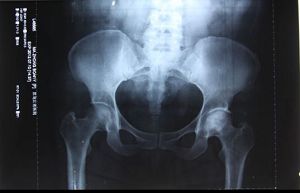

我说那我也不拍,好象我炼法轮功还不信任这个功法似的。屋里的几个病人听说我是背着来的,现在好了,都想看看我这股骨头恢复得如何。那些人也说:孩子你拍一个我们也看看啥样了。在大家的劝说下我拍了片子。拍完这个片子医生把最初来看病拍的那个片子拿出来对照,发现两个片子一模一样,大夫说你这腿也没好啊?看你这股骨头还跟烂土豆似的。看片子我的股骨头并没有变化,但我人却行动自如了。医生让我走、蹲给他们看,在我身上看不出股骨头坏死患者的任何症状,要不是张医生和片子作证,在场的所有医生和患者怎么会相信呢?我说这法轮功可神奇了,看你信不信,你信就有人管你。我说那片子有没有股骨头关我啥事呀,我能走我不疼就行呗,那我自己不疼我不知道啊。医生也说:对对,你不疼就行呗,管他片子啥样呢。

那篇文章,黑龙江省公安厅的人也看到了,去研究所调查我的事是否属实,张连喜医生实话实说的讲述了他亲眼见证了大法的神奇。医生把我的病例号(一九九九年三号)和二零零零年三月份拍的片子对比着讲给他们,两次拍片的结果都写着“双侧股骨头坏死”,但是炼法轮功后人是个健康的人了。省公安厅的人在那里也明白了事实真相,这件事就不了了之了。

二零一二年我又一次去了哈尔滨北方股骨头坏死研究所取片,那位所长又给我拍了个片子,结果仍然是股骨头坏死的症状。

我修炼后三天就把那么严重的股骨头坏死炼好了,我去了修炼前曾经看过病的省医院拍片,医学影像科的医生张明磊给我拍完片子,那个大夫就在X光检查报告单上确诊的“股骨头坏死”后面打了个问号,在诊断书的下面写着:“观察”两个字。但是他写出病例了,盖的章。他给我做各种检查我都正常,走道,蹲起都行,他很纳闷。我就问他,问号是啥意思?他说:你是股骨头坏死。你这不是好了吗?我说我们家人让我花钱来拍片,就想看看片子怎么样。片子是啥样呢就给写啥样,家人只想要片子。你这问号是啥意思,我到底是不是股骨头坏死?他说:是,是股骨头坏死。但是你哪都不疼,你不都正常了吗?他也不明白是怎么回事。他对我提出的问号很后悔,大夫的名章已经盖上了没有办法再改变了,也只好那样了,他一再说:是股骨头坏死,是股骨头坏死。

二零一二年七月十号在黑龙江省医院检查股骨头坏死的诊断。

二零零五年我在砖厂干活时,偶尔碰到一个当地的医生,他早听说了我的事,但是他没信,非要我拍个片子看看,我去了区医院,拍完片子后那个人问我:你吃啥药好的呀?我告诉他我是炼法轮功炼好的。拍片子的人说:哎呀,你太幸运了(意思是说,你的股骨头这样你还能走路)。等片子拿给大夫看的时候,那大夫看看片子瞅瞅屋里的人问:人呢?我问他:啥人哪?大夫说:病人呢?我说我就是。他以为我没听懂他的话呢,接着还问:我说的是拍片子的人,你听不懂话呀?我问的是拍片子的那个人!我也郑重的告诉他:我就是拍片子的那个人!那大夫很吃惊的问:啊!你是咋好的?我说我是炼法轮功炼好的。

这大夫就紧忙的把我的一堆片子一边往袋子里装,一边说:哎呀妈呀,你快回家炼去吧。我就问那大夫:我在你这花钱拍片子,你得给我看看我这片子啥样啊。大夫说:这片子上是没好,但是你这不是好了吗!你快回家炼去吧。

我把片子拿给那个当地医生看,他一看片子就说:你确实是股骨头坏死,这是真的呀。护士不怎么会看片子,就问那个大夫:这片子咋看能看出是股骨头坏死啊?那个大夫说:你看这侧,比较好的那个地方,这上面有骨纹,你再看这侧是透亮的,没有骨头也就没有骨纹。那大夫在事实面前终于相信了,他说:你这功炼得好,你好好炼吧!

我说我在医大,还有几个地方都看过病。他告诉我:医大门诊的那些人都是我的学生。然后他对我说:星期日下午患者少,你去医院我给你查一下。我和魏医生的儿媳、孙子如约去了医大的CT室,魏医生给我做了三样CT,腰部、腹部、臗部。我原来附件炎、肾炎、妇科病都很重,他说你的腹部没有病;又拍腰,说你没有腰间盘突出,腰也没病;然后又拍臗部,他一下就看到了,他惊讶的说:啊!你确实是股骨头坏死,而且还很严重。股骨头烂的只剩一半了,半个,扣不住了,就是这个轴没了呀。但魏主任说:“你好了,你的骨质密度特大,你的骨质特结实。”

我说:“这股骨头都烂没了,怎么能说好了呢?”魏主任说:“我们的这台CT机一千多万元呢,能把骨头切片到130个横断面看骨质的内部,你股骨头的密度特别大。所以我说你好了。”他又说:“现在你的片子上股骨头的这个样子,应该是根本就无法抬腿的。”我当时就把腿给他抬的高高的,我问他:你说咋抬吧?他说:这也太神奇了。